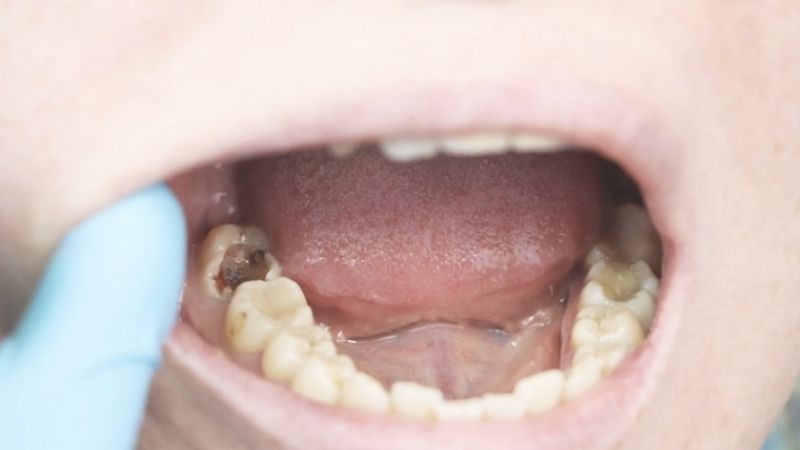

Sâu răng hàm là tình trạng tổn thương mô cứng của răng hàm do vi khuẩn trong khoang miệng tạo ra axit phá hủy men răng và ngà răng. Ở trẻ em, răng hàm thường là những chiếc răng sữa hoặc răng vĩnh viễn mới mọc, rất dễ bị sâu do cấu trúc men răng còn mềm và chưa hoàn thiện.

Răng hàm có vai trò quan trọng trong việc nhai, nghiền thức ăn, nên sâu răng tại vị trí này có thể ảnh hưởng lớn đến quá trình ăn uống và sức khỏe tổng thể của trẻ.